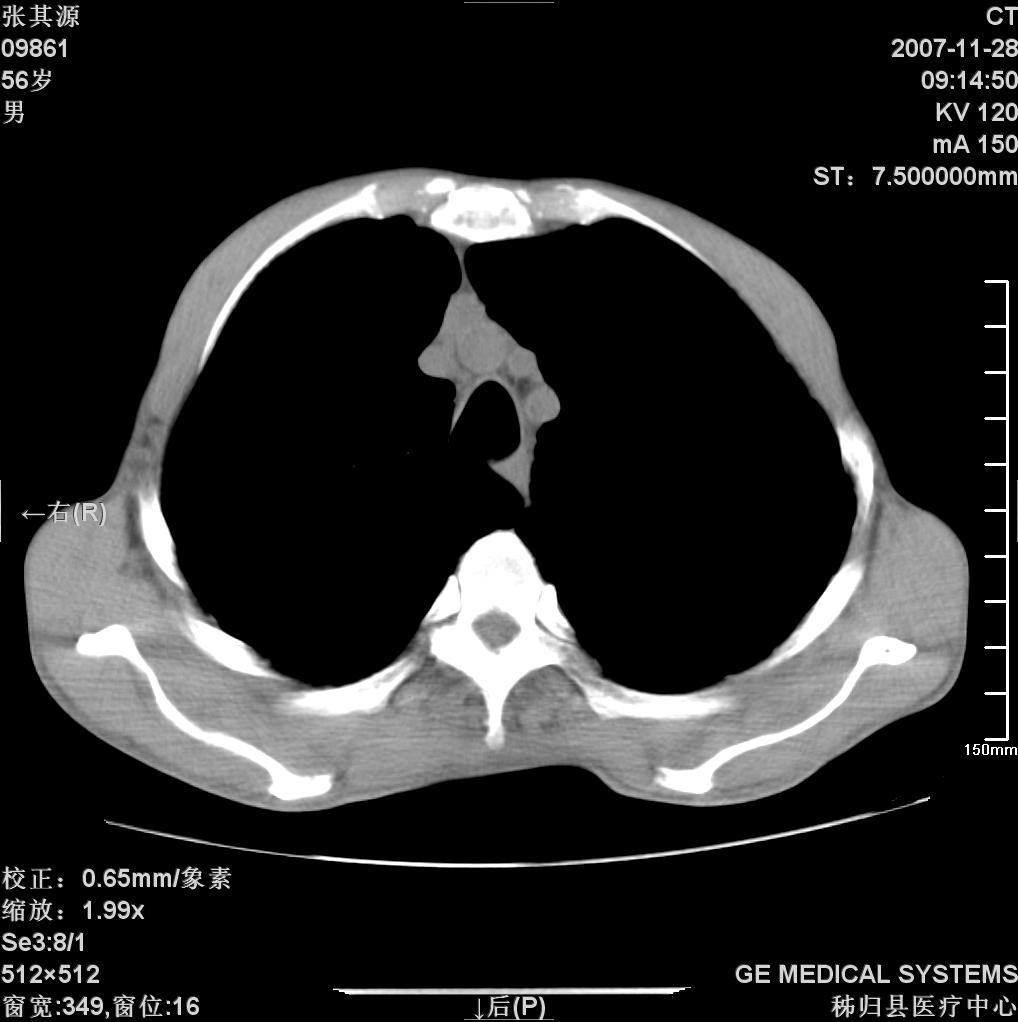

患者因阻塞性黄疸入院,发病前10天持续中等程度发烧.术前检查发现两肺弥漫性病变,请各位大虾会诊,除了考虑急性血源性肺结核外,还有其他什么疾病可能.

补充一下,该患者没有与尘肺相关职业史。请大家帮忙会诊一下,外科医生打算为其做胆总管肿瘤做手术的,现在在等我们的结果。谢谢各位了。

双肺多发粟粒样病灶,右肺胸膜下结节样病灶,气管前腔静脉后及隆突下均见肿大淋巴结,结合胆道肿瘤病史首先考虑转移。另外心影密度略低,时间格显示,是否有贫血?查明白再手术吧!